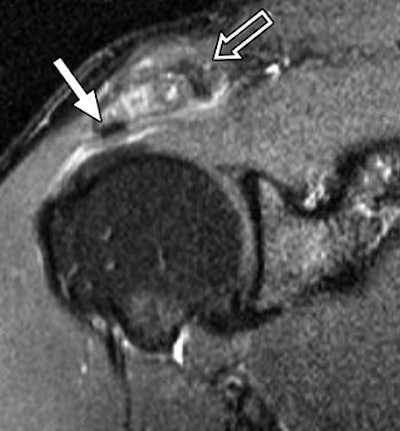

![]() |

| Same patient as above. Symptom duration was four months, and patient reported complete resolution of symptoms after six months of follow-up. Coronal oblique STIR MR image (TR/TE, 2,000/20; inversion time, 160 msec; echo-train length, 8) shows changes in acromioclavicular joint (open arrow) with osteophyte formation (closed arrow). Hambly N, Fitzpatrick P, MacMahon P, and Eustace SW, "Rotator Cuff Impingement: Correlation Between Findings on MRI and Outcome After Fluoroscopically Guided Subacromial Bursography and Steroid Injection" (AJR 2007; 189:1179-1184). |